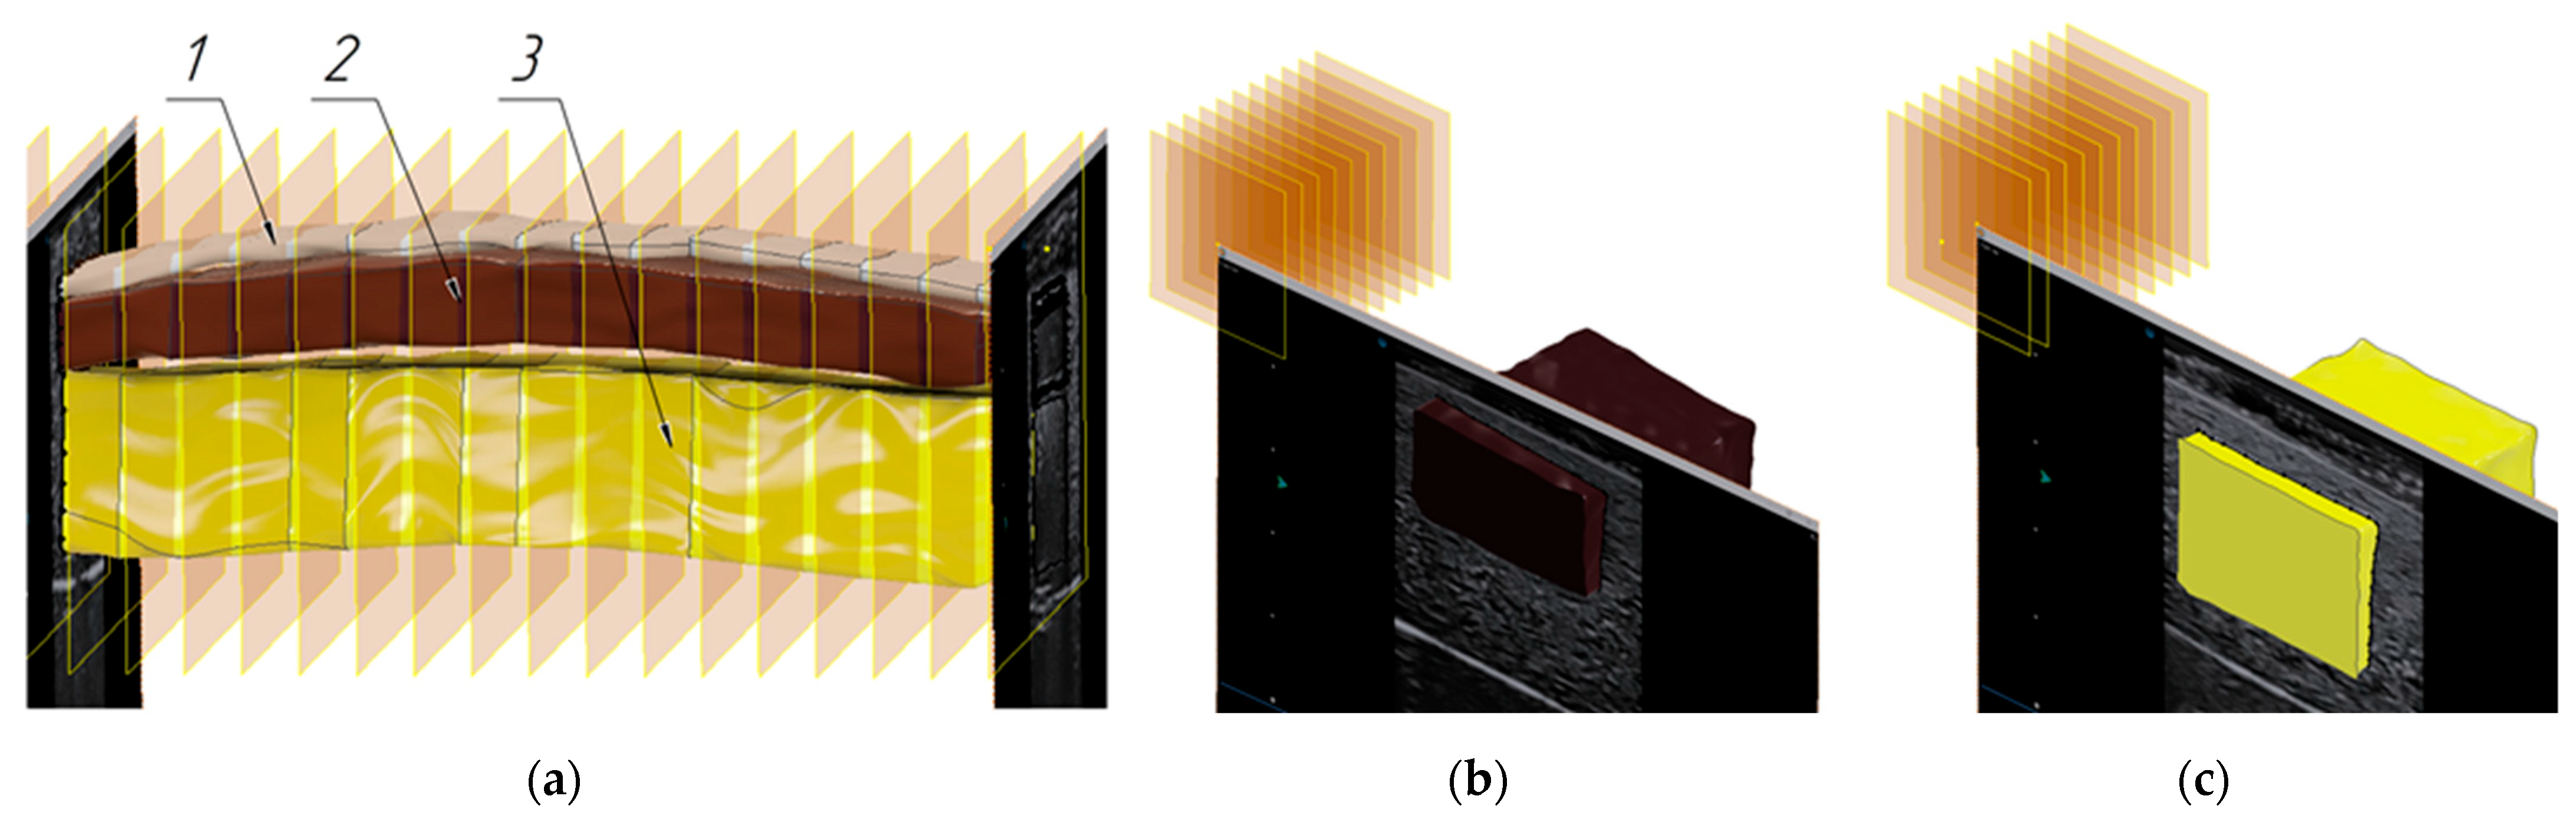

3.2. Verification of the Methodology for Constructing the Soft Tissue Volumetric Models